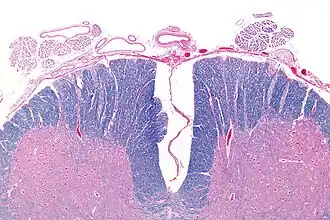

Micrograph showing an axial section of the anterior spinal cord and anterior spinal artery (top-middle of image). LFB-HE stain. | |